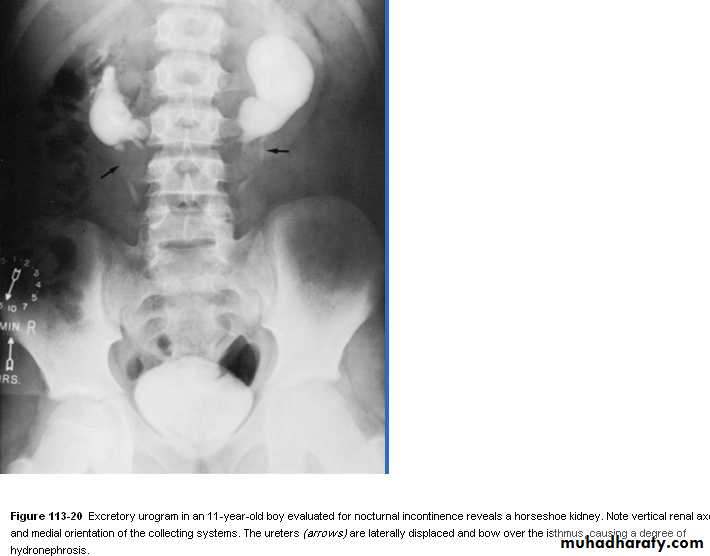

Horseshoe kidney

With hydronephrosisDifferent types of scalpel